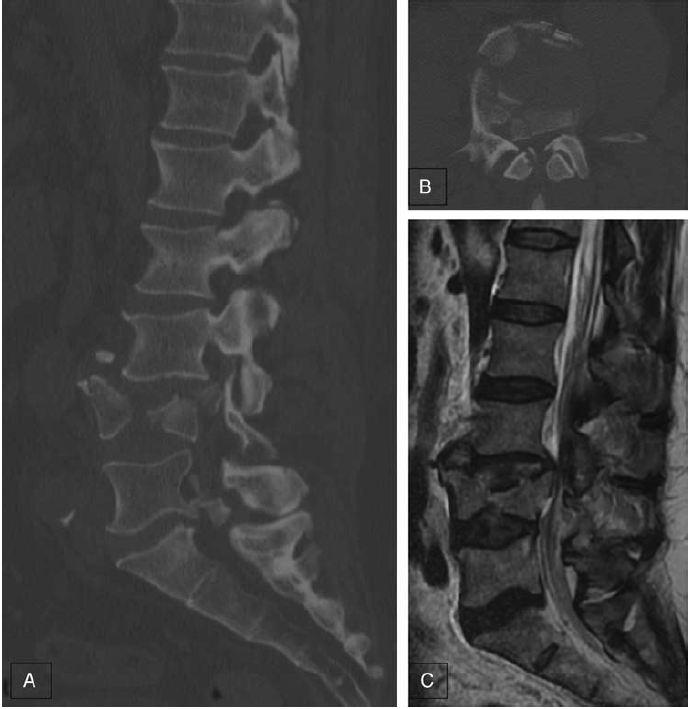

A, 三维CT矢状位示L4爆裂骨折三柱均有损伤;B, L4轴位图示骨折导致椎管内骨性狭窄;C,矢状位t2加权磁共振成像显示骨折碎片向后突入椎管。